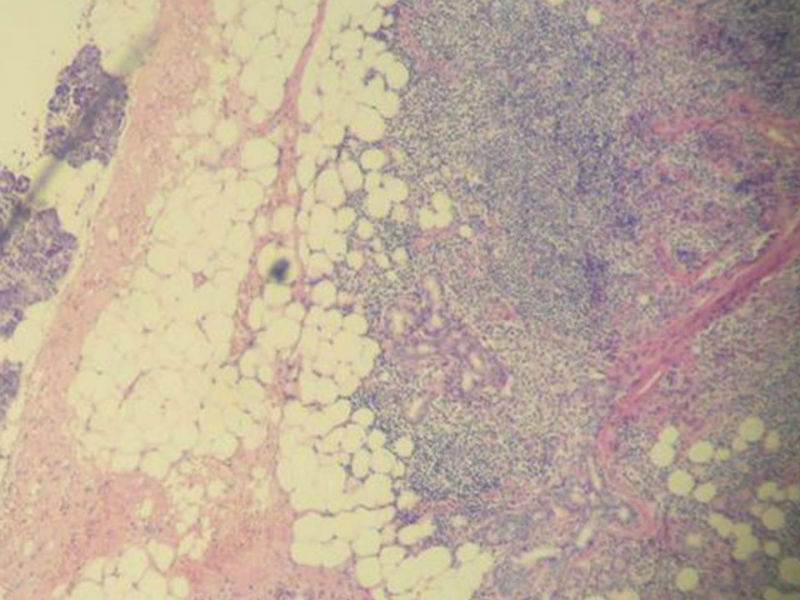

女,71岁,腮腺肿物,临床诊断混合瘤。

图2